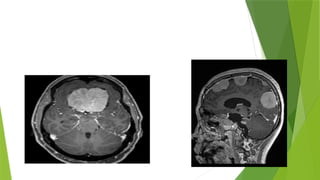

 Multiple variable sized extra axial broad base lesion are noted in bilateral

Para falx region, frontal and parietal lobes with average size of 1.3 x 1 cm.

 Multiple variablesized extra axial broad base lesion are noted in bilateral Para falx region, frontal and parietal lobes with average size of 1.3 x 1 cm.  Two other altered signal intensity lesion arising from 7th and 8th nerve are noted in left CP angle and protruding into left internal acoustic meatus giving appearance of ICE CREAM CONE. Returning signals are iso intense on T1 and T2 and showing avid enhancement on post contrast images and no restriction on DWI.  Multiple variable sized cervicomedullary and upper cervical cord shows intra medullary enhancing lesions having average size of 8 x4 mm suggestive of ependymoma.